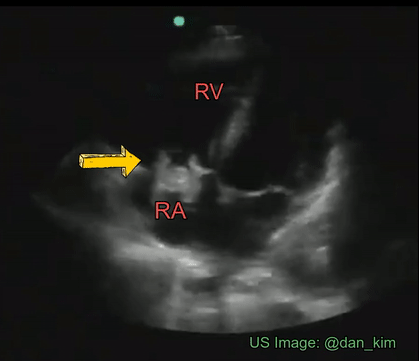

Identify the cardiac pathology demonstrated in the image.

Right atrial myxoma

Mitral stenosis

Tricuspid endocarditis/vegetation

Tricuspid stenosis